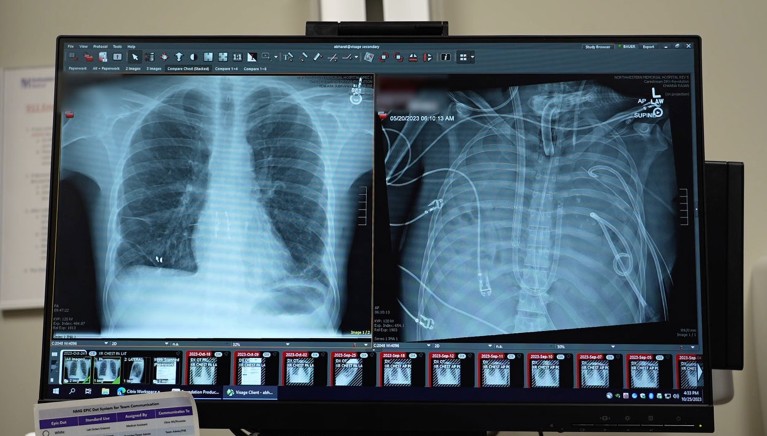

X-rays show a 33-year old patients’ new lungs (left) and old lungs (right).Credit: Northwestern Medicine

A 33-year-old man survived for 48 hours without his lungs, after a medical team replaced the organs with an external artificial-lung system1 that it developed to keep him alive until he could receive a double lung transplant.

Surprisingly, the man began to improve quickly. “Within 48 hours, he was off all the medication to support his blood pressure, his kidney function was completely restored and his heart was working normally,” says Bharat. At that point, the man received a double lung transplant and has showed no signs of organ rejection or impaired lung function years later. “We are now approaching almost three years since we did this, and the patient is doing really great,” says Bharat.